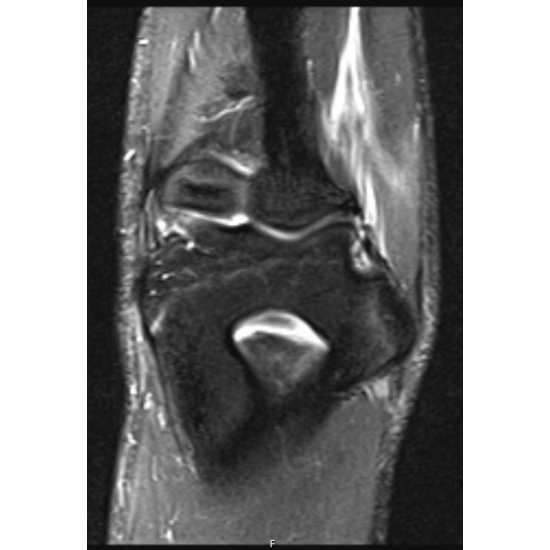

MRI Elbow: There was a complete tear of the distal anterior band ulnar collateral ligament. There were findings compatible with medial humeral epicondyle apophysitis Case Photo #2 . There was a chronic small avulsion fracture of the sublime tubercle. There were mild edematous changes about the ulnar nerve within the cubital tunnel.